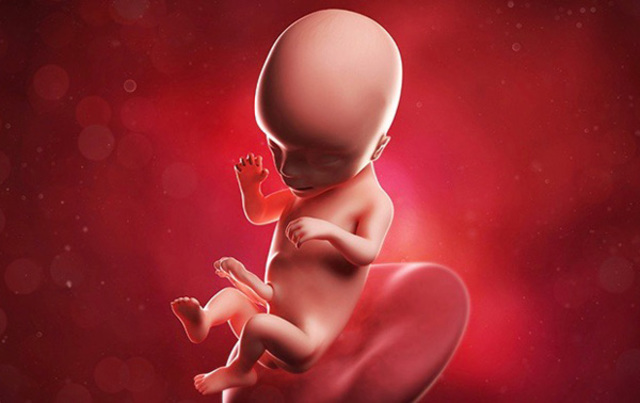

• Semana 15

Semana 15

-La piel del feto es casi transparente.

-El feto posee reflejo de succión.

• Semana 16

Semana 16

-El feto mide 14 cm.

-El SN funciona a pleno rendimiento.

-El cerebro poco a poco controla movimientos.

-Las manos se desarrollan antes que los pies, al mismo tiempo que se desarrollan los sentidos.

-Los ojos más juntos, aspecto más humano.

-El SNC extiende sus conexiones desde el cerebro a casi todas las partes del cuerpo.

-El cerebro asume control, regula músculos.

-Latidos: 140-150 pulsaciones por minuto.

-Es sensible al tacto.

-Ya tiene propiocepción